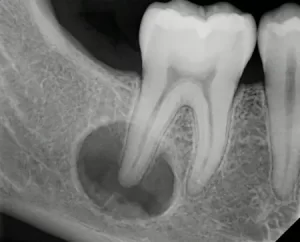

- Оценка размеров и состояния кисты по снимку челюсти пациента.